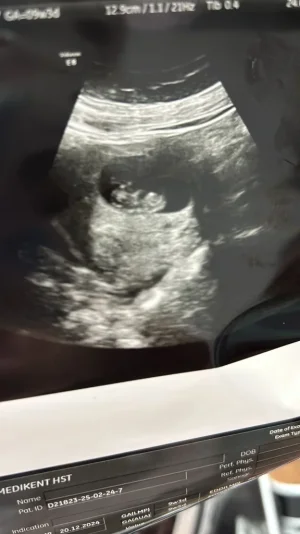

bizde bu gun 9 haftalık olduk